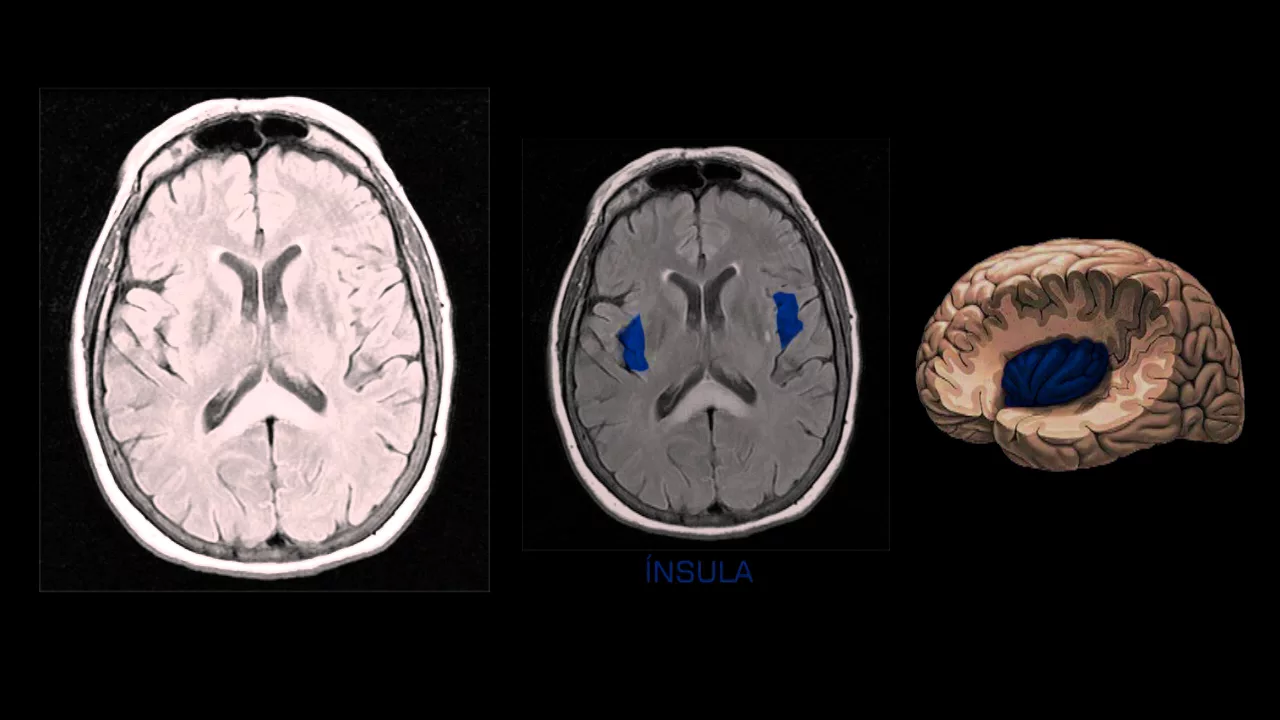

que é o suco lateral ou a fissura de silvios e ele é importante pra gente conseguir identificar e conseguir delimitar o que é lobo frontal do que é lobo temporal e de onde estaria por por exemplo o lobo da ínsula então aqui em verde eu destaquei o suco lateral ou fissura de silvios né em seguida o lobo temporal aqui em rosa essa parte para trás da fissura ou do suco de silvios o lobo ospital todo mundo já sabe aqui a gente vê o lobo em destacado em azul o lobo da ínsula que é um lobo

mais interno né dá para ver aqui nessa imagem à direita a última à direita colorida uma imagem do Netter com com o corte aqui na região temporal que dá para visualizar o lobo da ínsula eu não coloquei aqui as funções de cada um dos lobos eu vou deixar isso para um próximo vídeo eu vou colocar resumido o que cada Lobo corresponde a cada função vamos ver dá uma olhada nas estruturas né nas principais estruturas que podem ser visualizadas eu à medida do possível eu coloco sempre o corte sagital e o axial lado a lado pra